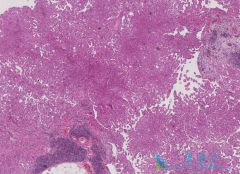

结肠癌是常见的发生于结肠部位的消化道恶性肿瘤。结肠癌的发病与社会环境、生活方式、遗传因素、年龄、结直肠息肉史、溃疡性结肠炎等有一定的关系。而 希罗达 (xeloda)是一个用于肿瘤科的药品,其中也包括治疗结肠癌。为了帮助大家更好的认识这个药品 ...

滤泡淋巴瘤(FL)通过利妥昔单抗( Rituximab )治疗得到改善。在瑞典,2003-2007年间,不同地区逐渐引入一线利妥昔单抗疗法。2007年首次发布的滤泡淋巴瘤国家指南建议利妥昔单抗作为一线疗法。   根据基于人群的瑞典淋巴瘤注册,2000-2010年,2641名患 ...